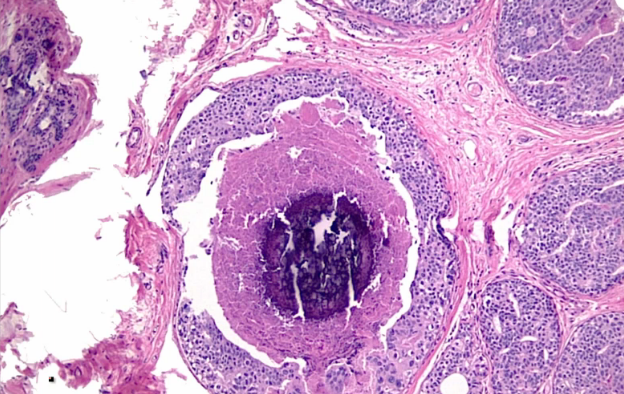

Breast cancer that is more commonly detected as calcification on mammography than a mass?

Ductal carcinoma in situ (Comedo type). When the malignant cells proliferate within the ducts, the center of the proliferation becomes necrotic. It also undergoes dystrophic calcification and shows up on mammography. It does not present as a mass because it is confined to the ducts.